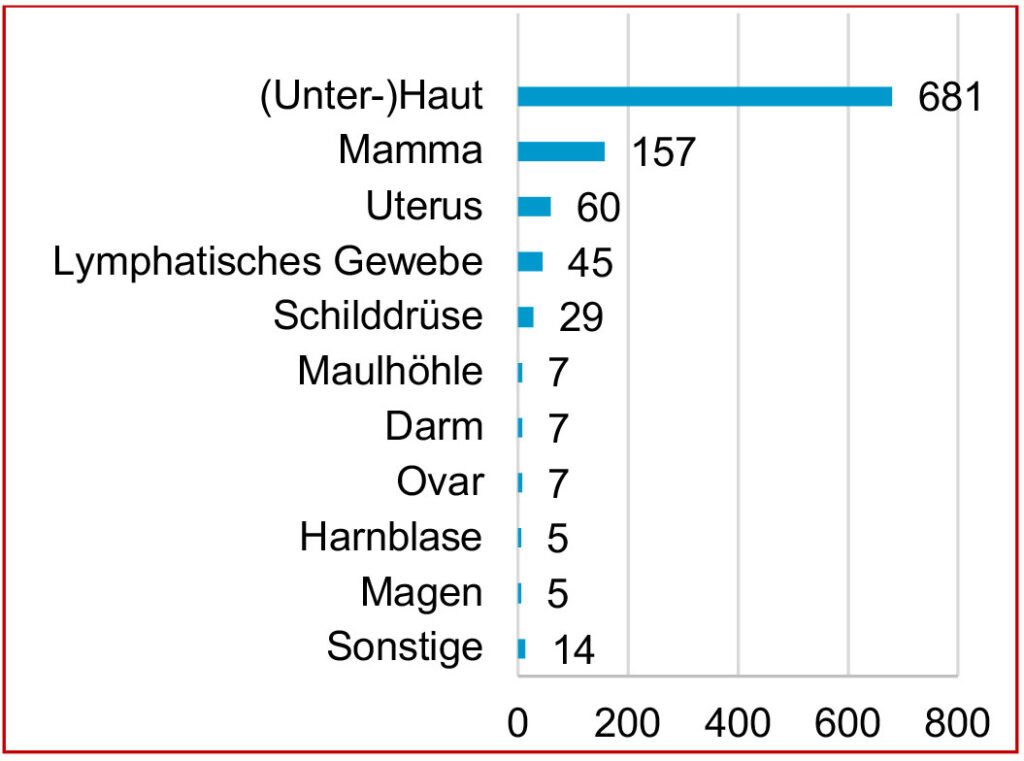

Die eingesandten Tumoren stammten aus unterschiedlichsten Lokalisationen, wobei die Tumoren der (Unter-)Haut am häufigsten zur Einsendung gelangten. Es folgten Tumoren aus dem Bereich des Mammadrüsengewebes, des Uterus und des lymphatischen Gewebes. Auch Schilddrüsentumoren waren vertreten. Neoplastische Veränderungen anderer Organe gelangten sehr viel seltener zur Einsendung (Abb. 1). Da Tumoren im Bereich der Haut und Unterhaut den Besitzern beim Handling und der Pflege der Tiere auffallen, ist dies vermutlich mit ein Grund, dass Neoplasien dieser Lokalisation am häufigsten zur Einsendung gelangten, während mögliche Prozesse innerer Organe dem Besitzer nicht zwangsläufig auffallen müssen, bzw. aufwendigere Operationen nötig machen würden.

Abb. 1: Tumorlokalisationen beim Meerschweinchen im Einsendungsgut von Laboklin (2013–2020)

Bildquelle: Laboklin